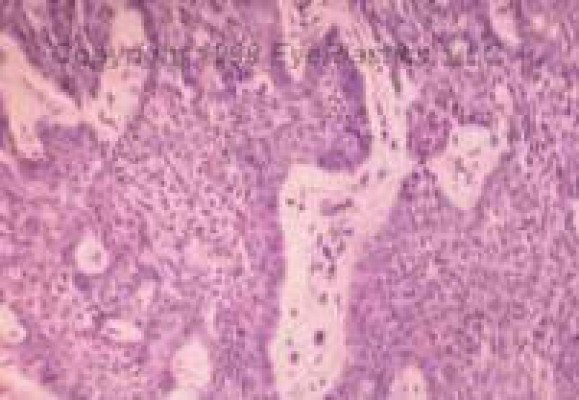

Basal Cell Carcinoma

Pigmented Basal Cell

Basal cell is the most common eyelid malignancy and occurs most commonly on lower lids, followed by medial canthus and upper eyelid.